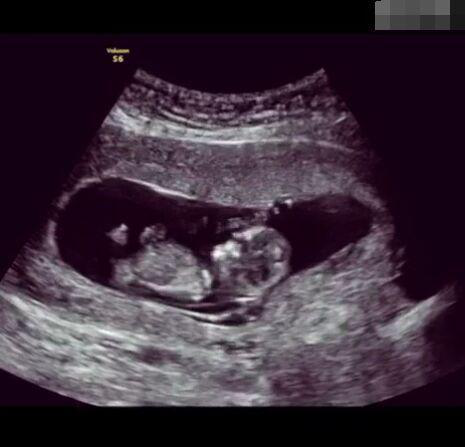

懷孕后,寶寶的性別一直是全家人的重點(diǎn)關(guān)注對(duì)象。而男女性別的差異,在基因?qū)用骟w現(xiàn)在第二十三對(duì)染色體上,如果是XY則是男孩,XX則是女孩,這都是由那枚與卵子結(jié)合的精子來決定。

圖片8.png

那些做了B超檢查確定胎兒男女,生下來后發(fā)現(xiàn)不對(duì)的,多半是因?yàn)樵贐超檢查時(shí)寶寶太調(diào)皮,以致影響了檢查準(zhǔn)確性。就比如說,有的女寶寶在媽媽肚子里玩自己的臍帶,把臍帶夾到了兩腿中間,B超就有一定幾率拍出來好像是男寶寶的特征,導(dǎo)致被誤認(rèn)為是男孩子。還有些男寶寶過分害羞,在做B超時(shí)雙腿緊緊并攏,醫(yī)生也很難判斷男女,只好大致猜測(cè)是女孩,就又造成了誤會(huì)。因此,B超亦不是萬能的。

其實(shí),不論男女都是父母的乖寶寶,不管是男孩還是女孩,都讓我們一起熱烈歡迎他們的到來吧!